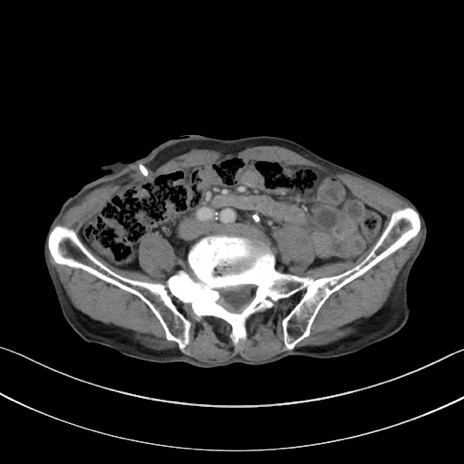

【症例】 70歳代男性

【主訴】右鼠径部腫瘤、疼痛

【現病歴】本日朝より上記主訴あり、受診。

【既往歴】膀胱癌にて膀胱全摘、両側尿管皮膚瘻

【データ】WBC 5600、CRP 0.56